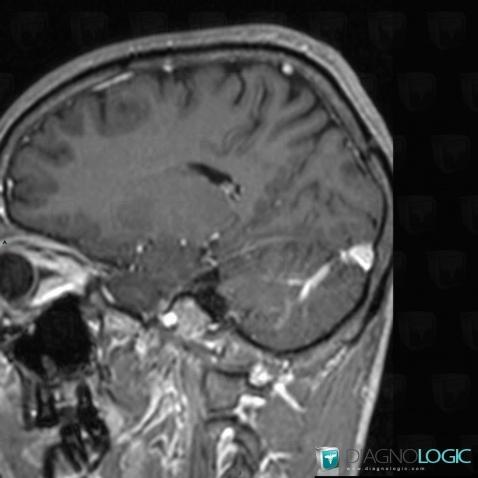

Voici les informations spécifiques à l'image clé ci dessus:

- Diagnostic Anomalie veineuse de développement, Localisation(s) Veines cérébrales, comportant les gammes Fosse postérieure, comportant les gammes Malformation congénitale du cerveau, Lésion infratentorielle à réhaussement intenseHémisphère cérébelleux, comportant les gammes Lésion cérébelleuse